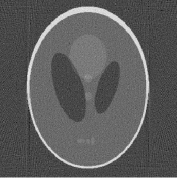

We use the Shepp-Logan phantom, available, for instance, in the Matlab Image Processing toolbox (see Figure 1). The phantom is sized , with . The projection data (i.e., sinogram) of the simulated phantom is corrupted by a white Gaussian process with zero mean and variance.

The reconstructions of the Shepp-Logan phantom are shown in Figure 4. Plots of the sparsity levels, as the iteration progresses, are reported in Figure 6. For the 120 projections case, the proposed approach converges in 885 iterations, while, in the 30 projections case, it converges in 301 iterations. As figure of merit, we use the relative error: the obtained values are summarized in Table 2, where we also report the values of the relative error obtained for the FBP reconstructions.